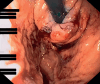

Combining transoral fundoplication and robotic cruroplasty: a novel robotic-assisted endoscopy